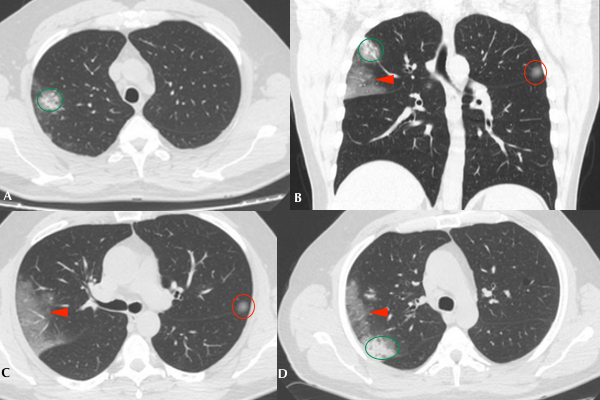

Se realizó TC de tórax a 85 (5,9%) pacientes, de los cuales 11 (13%) fueron positivos por PCR para COVID19. De estos, 9 (81%) manifestaron infiltrados en vidrio esmerilado en el parénquima pulmonar, asociándose además opacidades consolidativas en 4 (36%) de ellos (Figs. 3 y 4). 2 (18%) pacientes no mostraron afectación intersticio-alveolar en su evolución. La TC se realizó a pacientes cuya clínica no era acorde a los hallazgos de Rx y a aquellos con evolución tórpida (81%). En total, a 8 (72%) pacientes COVID-19 positivos se les realizaron ambos métodos imagenológicos.

En cuanto a la distribución, en los cortes axiales se encontró que siete pacientes presentaron opacidades o consolidaciones periféricas, o ambas (Figs. 5 y 6).

La cantidad de lóbulos afectados fue variable. Un paciente presentó afectación lobar única, uno afectación bilobar, cuatro afectación de tres lóbulos y dos pacientes de cuatro lóbulos. Únicamente un paciente sufrió compromiso panlobar (Fig. 7). Los lóbulos pulmonares con mayor afectación fueron los superiores: siete pacientes tuvieron afectación del lóbulo superior derecho y ocho pacientes del lóbulo superior izquierdo. Cabe mencionar, además, que ocho pacientes tuvieron afectación bilateral y uno unilateral.

En un paciente se encontró patrón en empedrado (Fig. 8) y en dos pacientes opacidades redondeadas en vidrio esmerilado (Tabla 1).